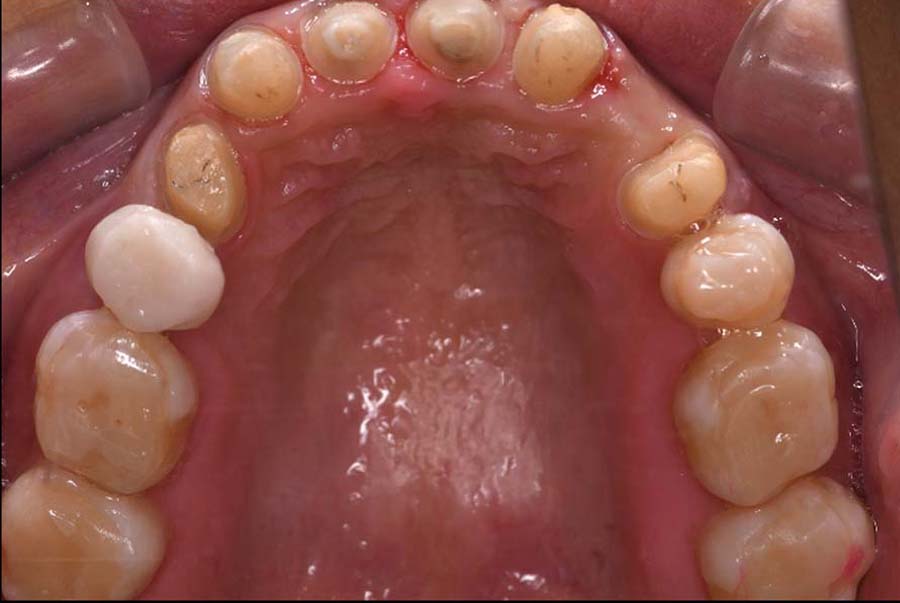

治療内容 ①スプリントを装着

②副子を装着

③2024年4月 口腔内反映開始

④副子を入れた状態の所まで咬合を挙上

(バイトアップ)

⑤2024年5月 上顎前歯部8本へ仮歯(TEK)

を装着

初診日 2023年10月12日